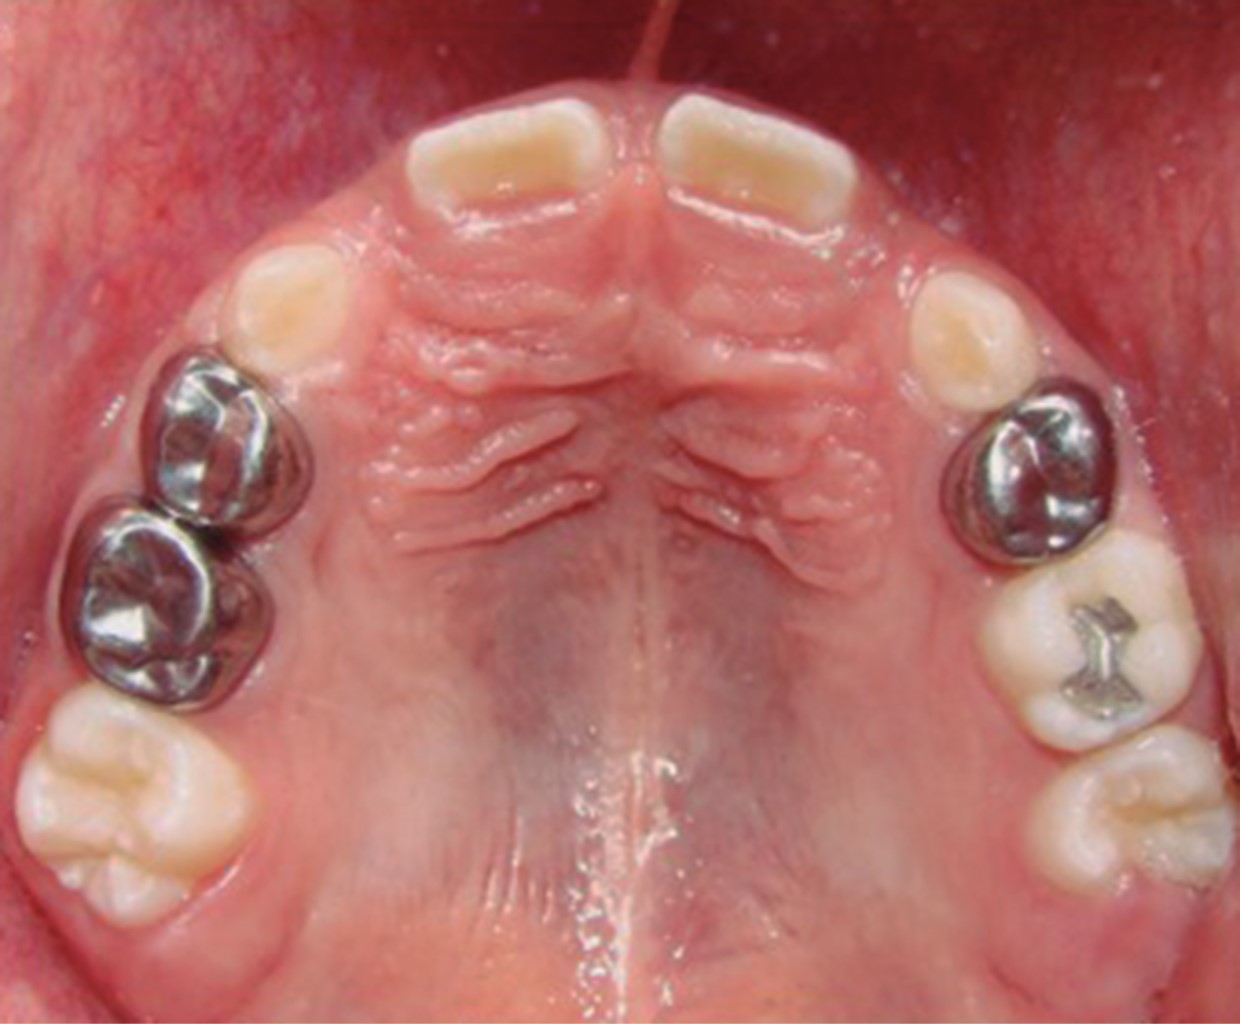

Figure 1